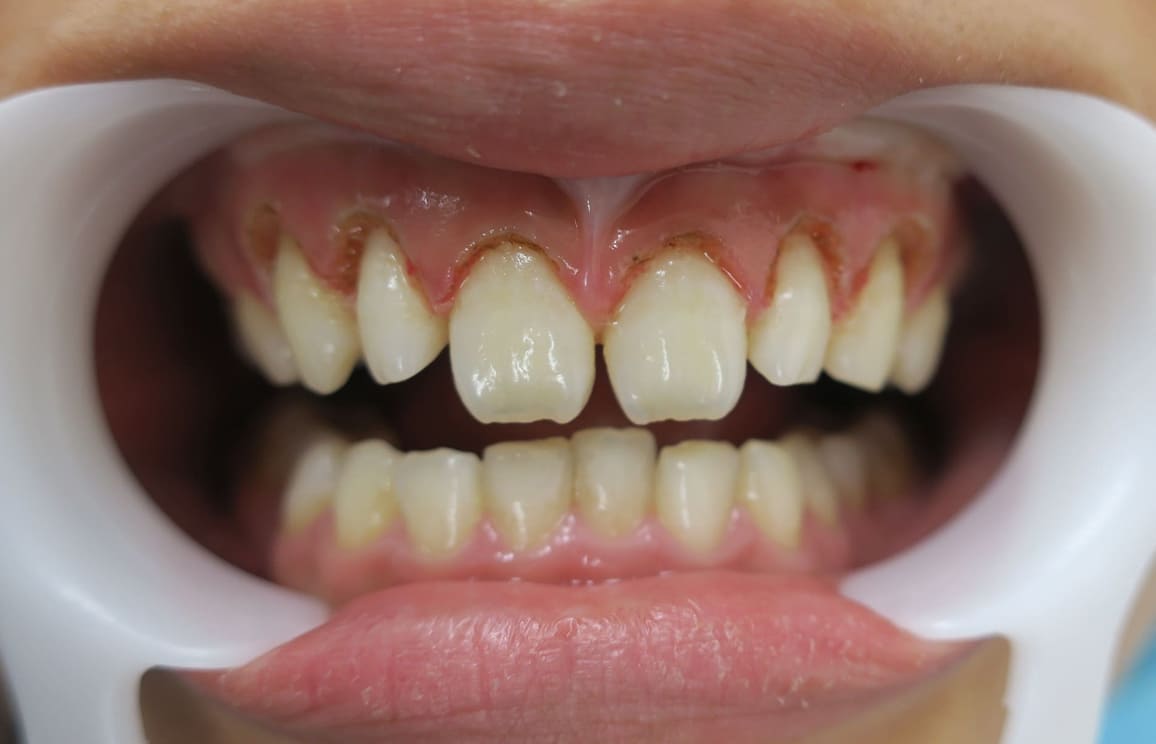

藤沢デンタルオフィスのホワイトニング術前 藤沢デンタルオフィスのホワイトニング術後

術前

術後